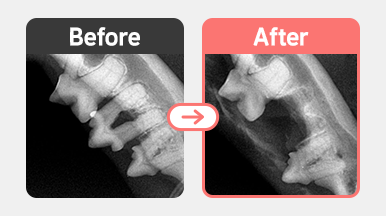

치아흡수성병변